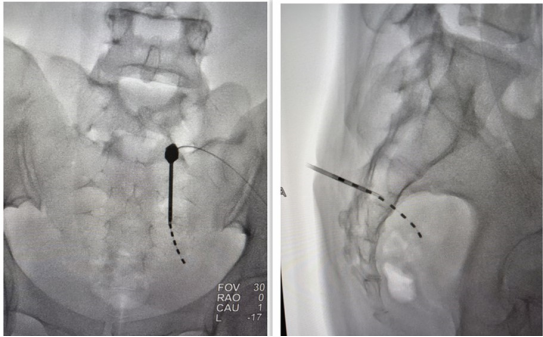

术中图片